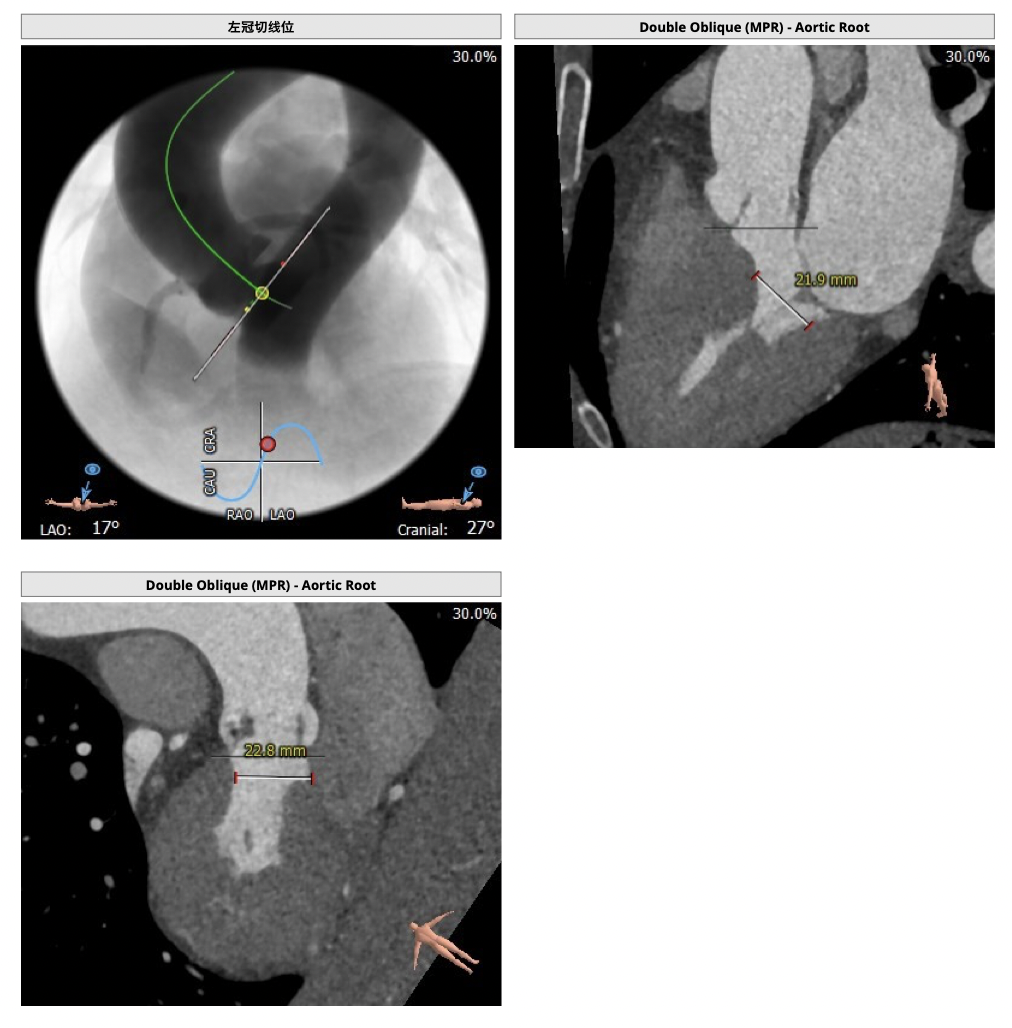

制定策略:

经分析研判,拟从右侧股动脉穿刺入路,使用20mm球囊预扩,采取downsize手术策略,选用L23号的VenusA-Valve瓣膜,因患者为横位心,瓣膜释放同轴性差,容易发生移位,故采用VenusA-Plus可回收输送系统确保瓣膜的稳定释放,瓣膜释放后结合造影和超声情况,决定是否后扩。